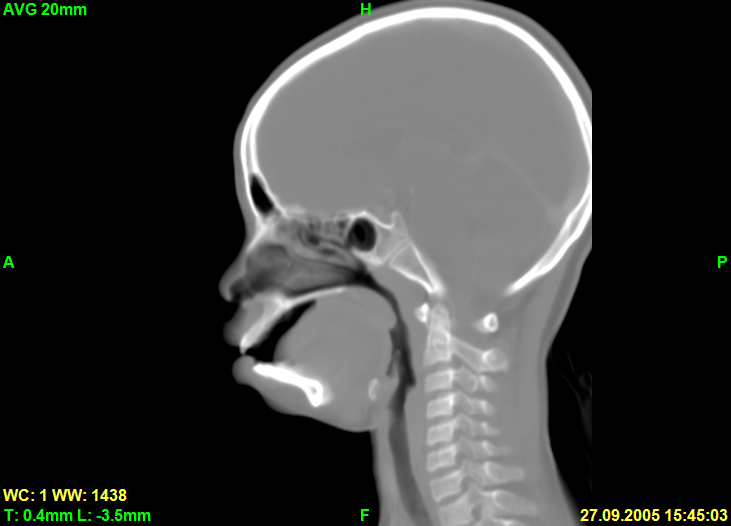

Вот скриншот сагиттального среза в режиме рендеринга Avg: